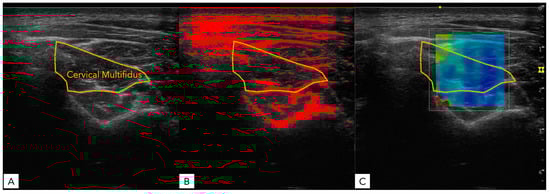

2.4.3. B-Mode Ultrasound and Shear Wave Elastography Analysis